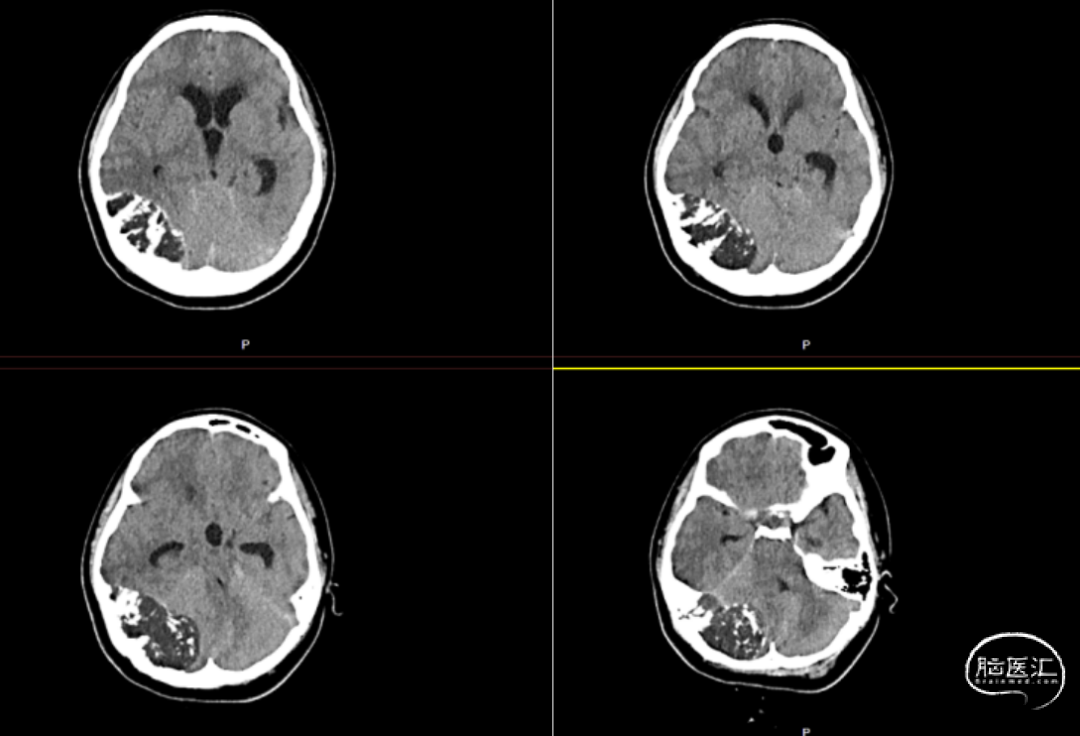

患者入院完善术前检查,头颅CT提示:右侧小脑半球-枕叶混杂密度肿块,大小约71*37mm,内见钙化,邻近颅骨骨质破坏、变薄,第四脑室受压(图1、图2)。进一步完善头颅增强MRI提示右侧颞枕部占位,脑外起源考虑,软骨肉瘤可能,血管瘤型脑膜瘤或血管瘤待排(图3)。

图1. 头颅CT影像,见右侧小脑半球-枕叶混杂密度肿块,大小约71*37mm,内见钙化。

本例颅内软骨黏液样纤维瘤的影像学表现典型,CT与MRI可辅助术前评估肿瘤边界及与周围结构的毗邻关系。CT可清晰显示边界清晰的溶骨性病变,伴边缘硬化及周围骨结构改变,但钙化检出率较低(约13%),多见于颅面部CMF或年轻患者[1]。组织学中钙化检出率更高(约35%),颅底CMF的细胞内钙化比例可达75%[2],本例患者CT与组织学均证实钙化存在(图1)。 MRI在确定病变范围方面比CT更有效。肿瘤在T1加权像上呈低信号,T2加权像上呈高信号,增强后显著强化,周围可能有软组织肿胀。通常由于纤维、软骨样和粘液样成分的组成不同,T2-STIR或T2加权脂肪抑制图像显示中等到高信号[5]。此外,MRI能清晰显示病变周围正常血管结构,对制定手术方案至关重要[2]。